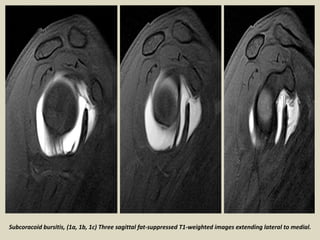

Subcoracoid bursitis, (1a, 1b, 1c) Three sagittal fat-suppressed T1-weighted images extending lateral to medial.

Subcoracoid bursitis.